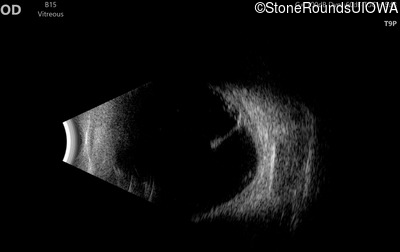

Visit at age: 12 years (Visit 2)

B-Scan Ultrasonography - Right - 20/600

Exemplar